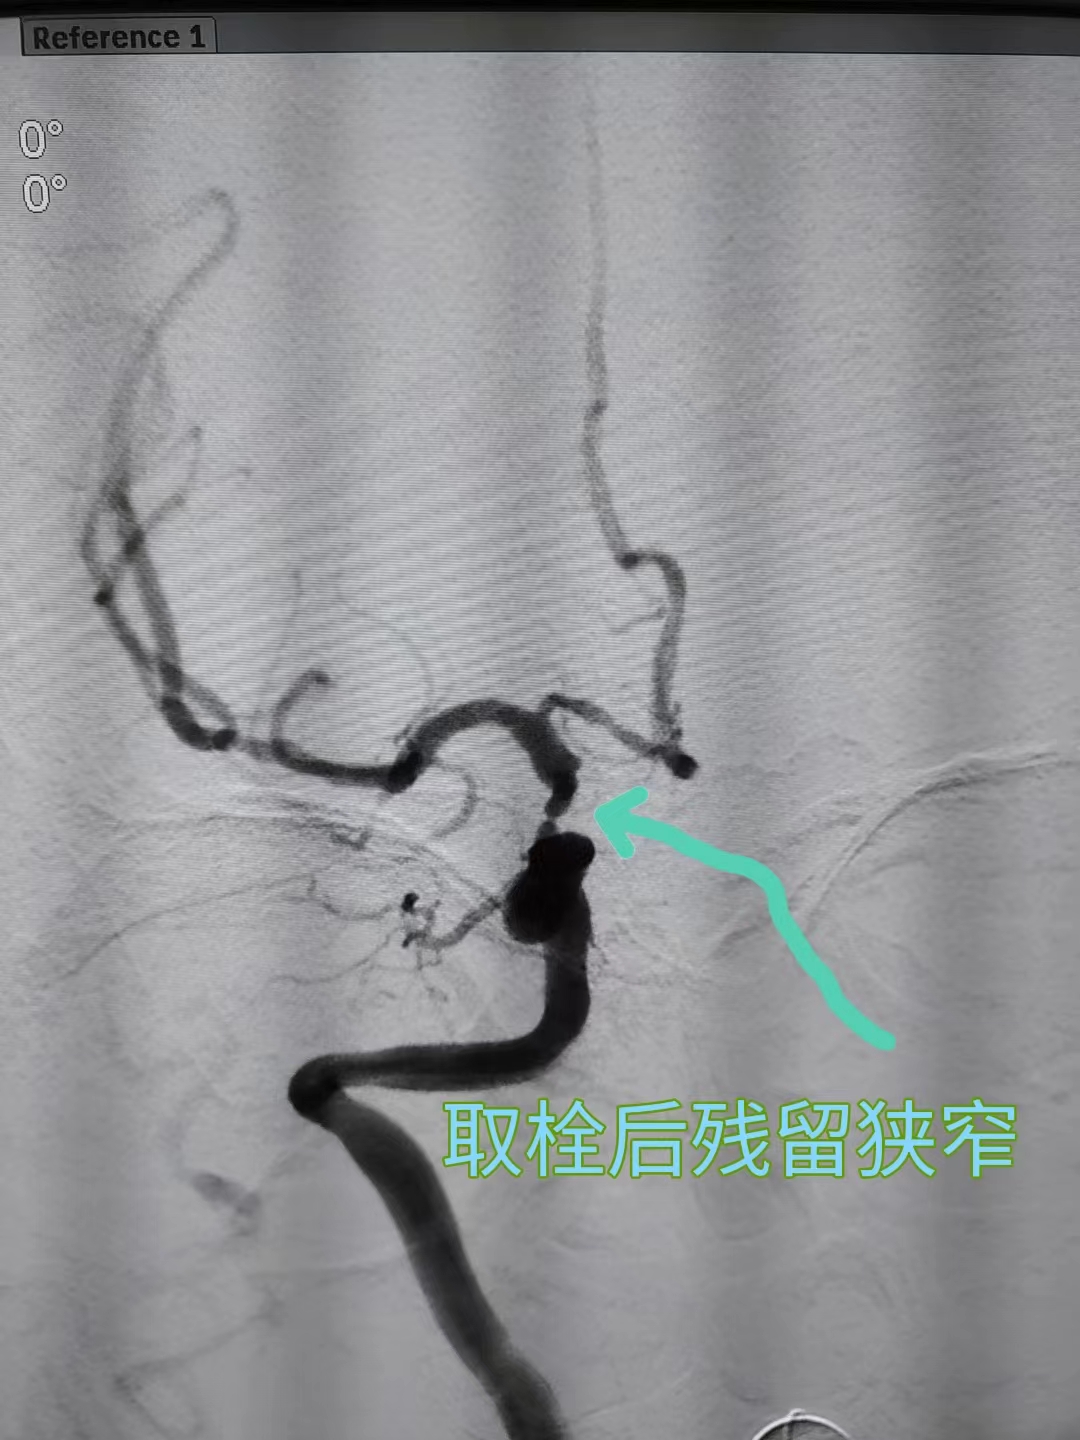

介入取栓后发现颈内动脉末端残留重度狭窄

取栓治疗主要是针对颅内大血管闭塞。通过导管经血管内到达闭塞部位,使用特殊的取栓装置将血栓取出,恢复闭塞部位血流。

时间就是大脑!0:09,神经内科团队为郑阿姨给予阿替普酶静脉溶栓,之后立即将其送至导管室进行介入取栓,30分钟后成功将血栓取出,45分钟成功将狭窄的颈动脉扩张成形实现血管再通。